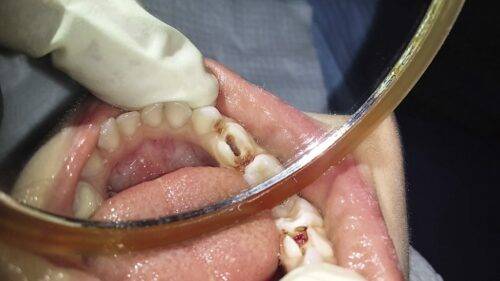

Как известно врачам, форм и разнообразий пульпита огромное множество. Не всегда представляется возможным вовремя диагностировать данное заболевание, поскольку маленький пациент, в отличие от взрослого редко точно описывает собственные ощущения, а также случаются формы никак не определяемые вовсе.

Именно потому так важно обнаружить, и начать лечение пульпита молочных зубов своевременно.